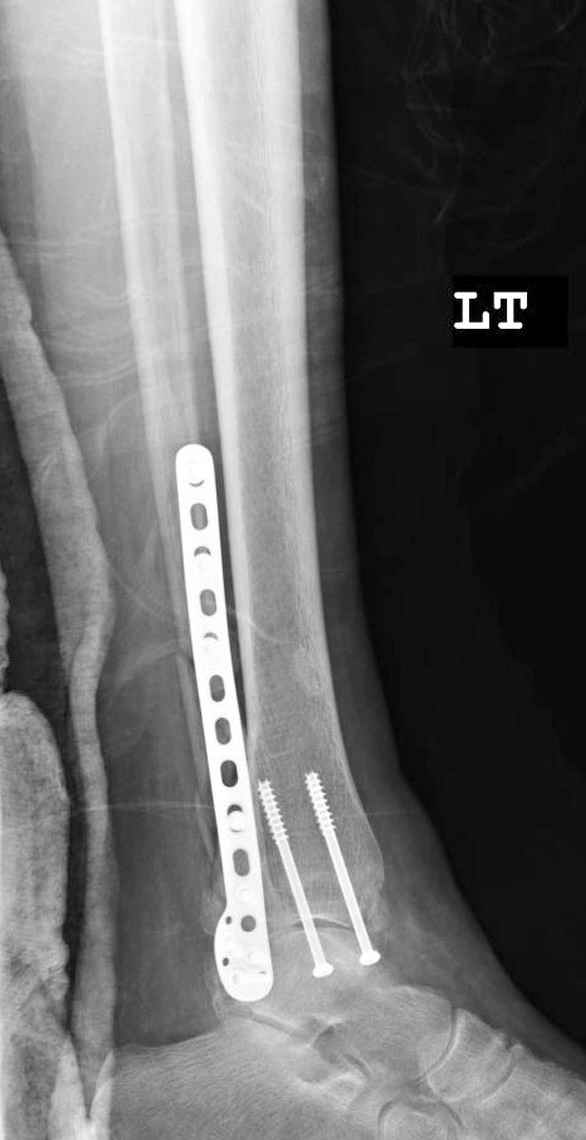

Малоберцовая выглядит коротковатой. Профиль как-то мутный. Вообще, неплохо было бы сделать снимки в сравнении со здоровой.

> Малоберцовая выглядит коротковатой. Профиль как-то мутный. Вообще,

> неплохо было бы сделать снимки в сравнении со здоровой.

> Малоберцовая выглядит коротковатой. Профиль как-то мутный.

Конечно, малоберцовая укорочена, надо сделать косой - мортиз снимок, тогда будеть понятно, на сколько.